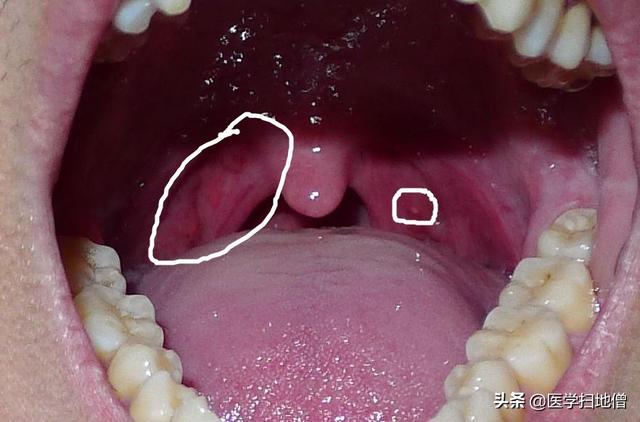

Une sensation de corps étranger dans la gorge est généralement observée dans le service ORL. La laryngoscopie est donc essentielle, et si l'examen révèle une hypertrophie pharyngée, une congestion et une hyperplasie folliculaire lymphoïde, vous pouvez être sûr qu'il s'agit d'un corps étranger dans la gorge.pharyngite chroniqueSi l'on observe une hypertrophie et une congestion des amygdales, laAmygdalite chronique. Mais l'inflammation de l'épiglotte n'est pas la seule cause de la sensation de corps étranger dans la gorge.Sinusite, reflux gastro-œsophagien, etc.Elle peut également entraîner des symptômes cliniques similaires, c'est pourquoi une gastroscopie est également pratiquée si nécessaire.

La première réaction de nombreuses personnes face à une gêne dans la gorge est de penser à une pharyngite. La pharyngite chronique est en effet l'une des causes les plus importantes de la gêne dans la gorge. Les personnes souffrant de pharyngite chronique éprouvent souvent une sensation de corps étranger dans la gorge, se sentent mal à l'aise dans la gorge et se raclent souvent la gorge. Si le diagnostic fait état d'une congestion de la muqueuse pharyngée, d'une hyperplasie folliculaire lymphoïde et d'autres problèmes, il est probable qu'il s'agisse d'une pharyngite chronique.

2) Amygdalite chronique

Si l'examen du pharynx montre une congestion des amygdales, des cicatrices ou la présence de bouchons de pus au niveau des orifices de la crypte, on peut déterminer que les amygdales sont chroniques. Cette maladie provoque également une sensation de gêne dans la gorge.

Il s'agit d'une maladie fréquente dans les consultations externes d'ORL, que nous appelons anisotropie pharyngée, qui est appelée plum nucleus qi en médecine chinoise, et la raison de la visite du patient est qu'il a l'impression d'avoir un corps étranger dans la gorge en permanence, qu'il ne peut pas l'avaler et qu'il ne peut pas le cracher, et l'examen de la consultation externe a révélé une hyperplasie des follicules lymphoïdes dans la paroi postérieure du pharynx et la racine de la langue, ce qui est considéré comme une pharyngite chronique. Mais cette maladie ne peut pas être expliquée par la pharyngite chronique, les enfants, les jeunes et les personnes âgées peuvent contracter cette maladie. Chez les enfants, la sinusite peut provoquer une pharyngite en raison de l'irritation du reflux du mucus nasal, de sorte que le traitement doit s'attaquer à la cause profonde du problème. Les personnes âgées peuvent être accompagnées d'un hoquet de reflux acide, d'une sensation de brûlure dans la gorge, il faut envisager une gastrite chronique, un reflux acide causé par une pharyngite de reflux, il faut traiter avec un antiacide en même temps. L'examen d'une pharyngite chronique simple sans autre maladie peut faire l'objet d'un traitement symptomatique par la médecine chinoise.

L'allodynie pharyngée est un état dans lequel il n'y a pas de lésion organique évidente dans le pharynx, mais le pharynx a une sensation anormale de corps étranger, de blocage, d'adhérence de mucosités ou d'inconfort. Les causes de l'allodynie pharyngée sont nombreuses et proviennent principalement de lésions organiques, telles que l'inflammation chronique des voies respiratoires supérieures, l'hypertrophie des amygdales, l'allongement de la luette, l'allongement du processus caverneux, la spondylose cervicale, l'inflammation de l'œsophage pharyngé ou du potentiel gastro-intestinal, les ulcères, les cancers précoces, les maladies systémiques, telles que le diabète sucré, l'anémie, les troubles thoraciques et abdominaux, les syndromes de la ménopause chez la femme, etc.